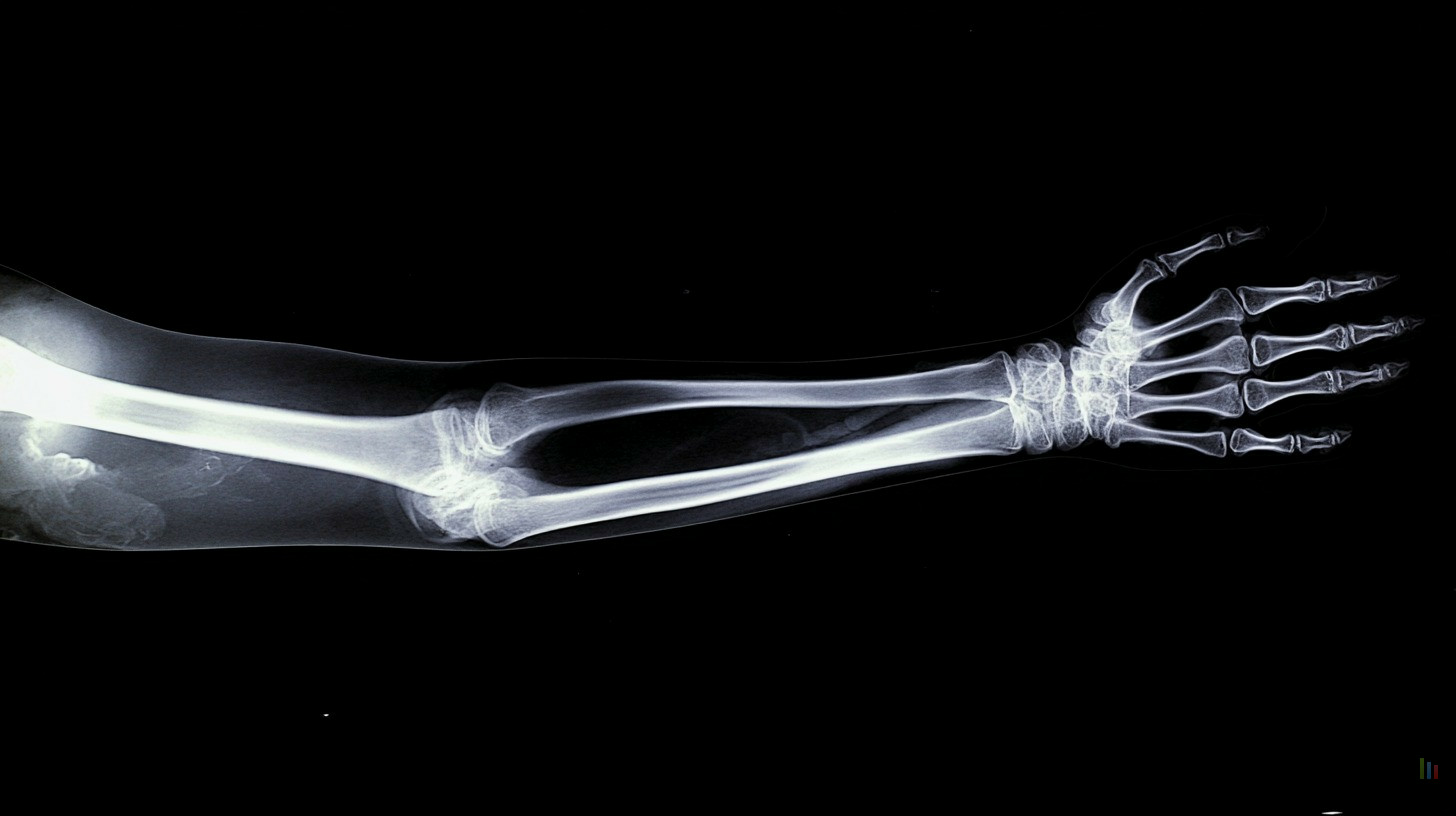

fracture 02

Soyons clairs : la réponse est non, et c'est tant mieux. Comme le souligne le Dr Mark Jenkins, l'intelligence artificielle agit ici comme un "super-assistant", pas comme un remplaçant du corps médical. Dans les tests menés par le NHS England, notamment dans le Lincolnshire, le logiciel génère une version annotée de la radio quasi instantanément pour guider le praticien.

Le médecin garde toujours le dernier mot pour établir le diagnostic final, mais il profite désormais d'une paire d'yeux virtuelle qui ne cligne jamais. C'est une collaboration homme-machine pragmatique qui valorise l'expertise humaine tout en gommant ses faiblesses.